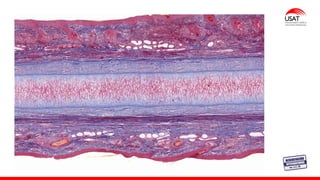

Membrana timpánica

Membrana vestibular

(de Reissner)

compuesta de dos capas de epitelio escamoso

separadas entre sí por una lámina basal

Membrana

basilar

La zona

arqueada

pectinada

Es más delgada, su

posición es más medial y

apoya el órgano de

Corti.

Es similar a una red

fibrosa y contiene

unos cuantos

fibroblastos.